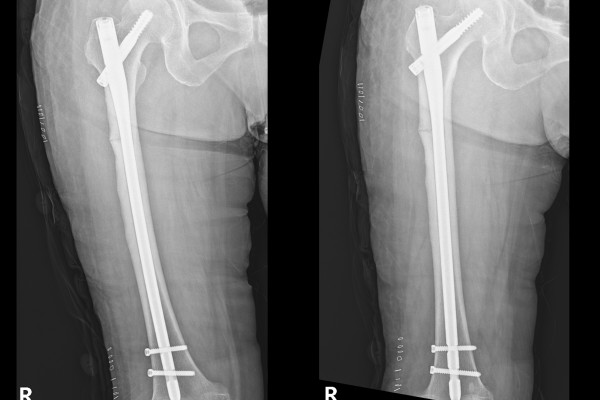

골절이 발생한 대퇴골 뼈 안에 말뚝 같은 기둥을 삽입하여 골절된 부위를 고정하는 방식의 수술,

대퇴골수강내 금속정 고정술 (Closed reduction c Long IM nail fixation for Atypical subtrochanteric Fx.)을

진행하였습니다.

수술은 순조롭게 마무리 되었고, 환자분께서는 수술 다음날 바로 서는 연습과 한 두 발자국씩 걷는 연습을 시작하셨습니다. 수술 결과에 크게 만족하신 환자분의 동의하에 사진촬영을 진행하였습니다.